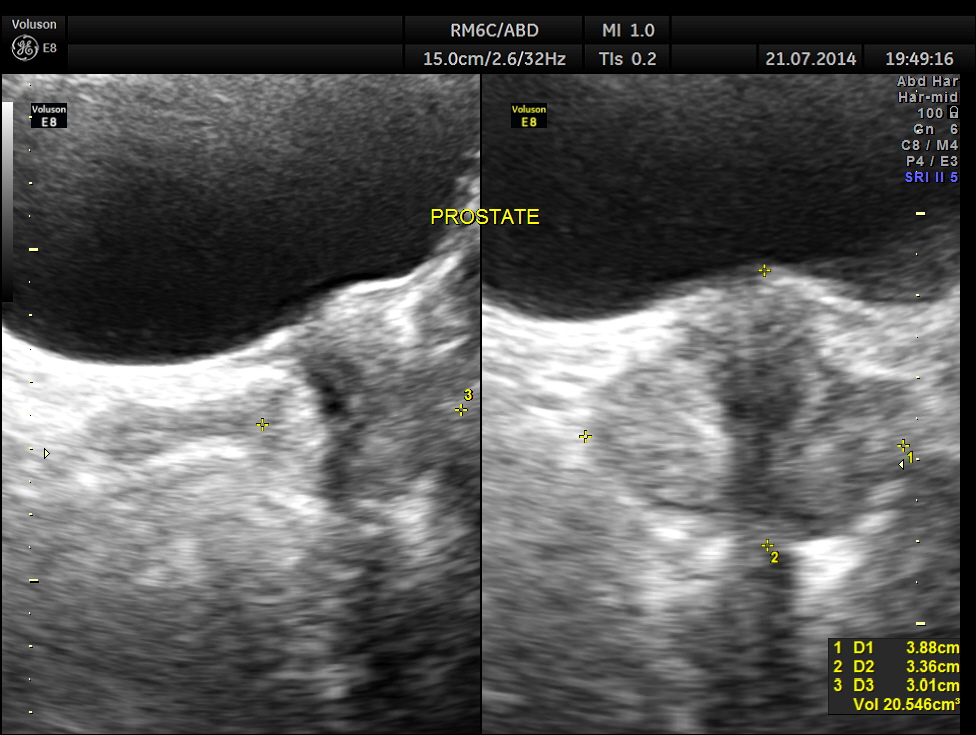

This was a 42-year-old gentleman , a known case of Insulin dependant Diabetes Mellitus. He was being evaluated by his physician for loss of weight and abdominal pain of a few months duration.

His abdominal ultrasound pictures are given below.